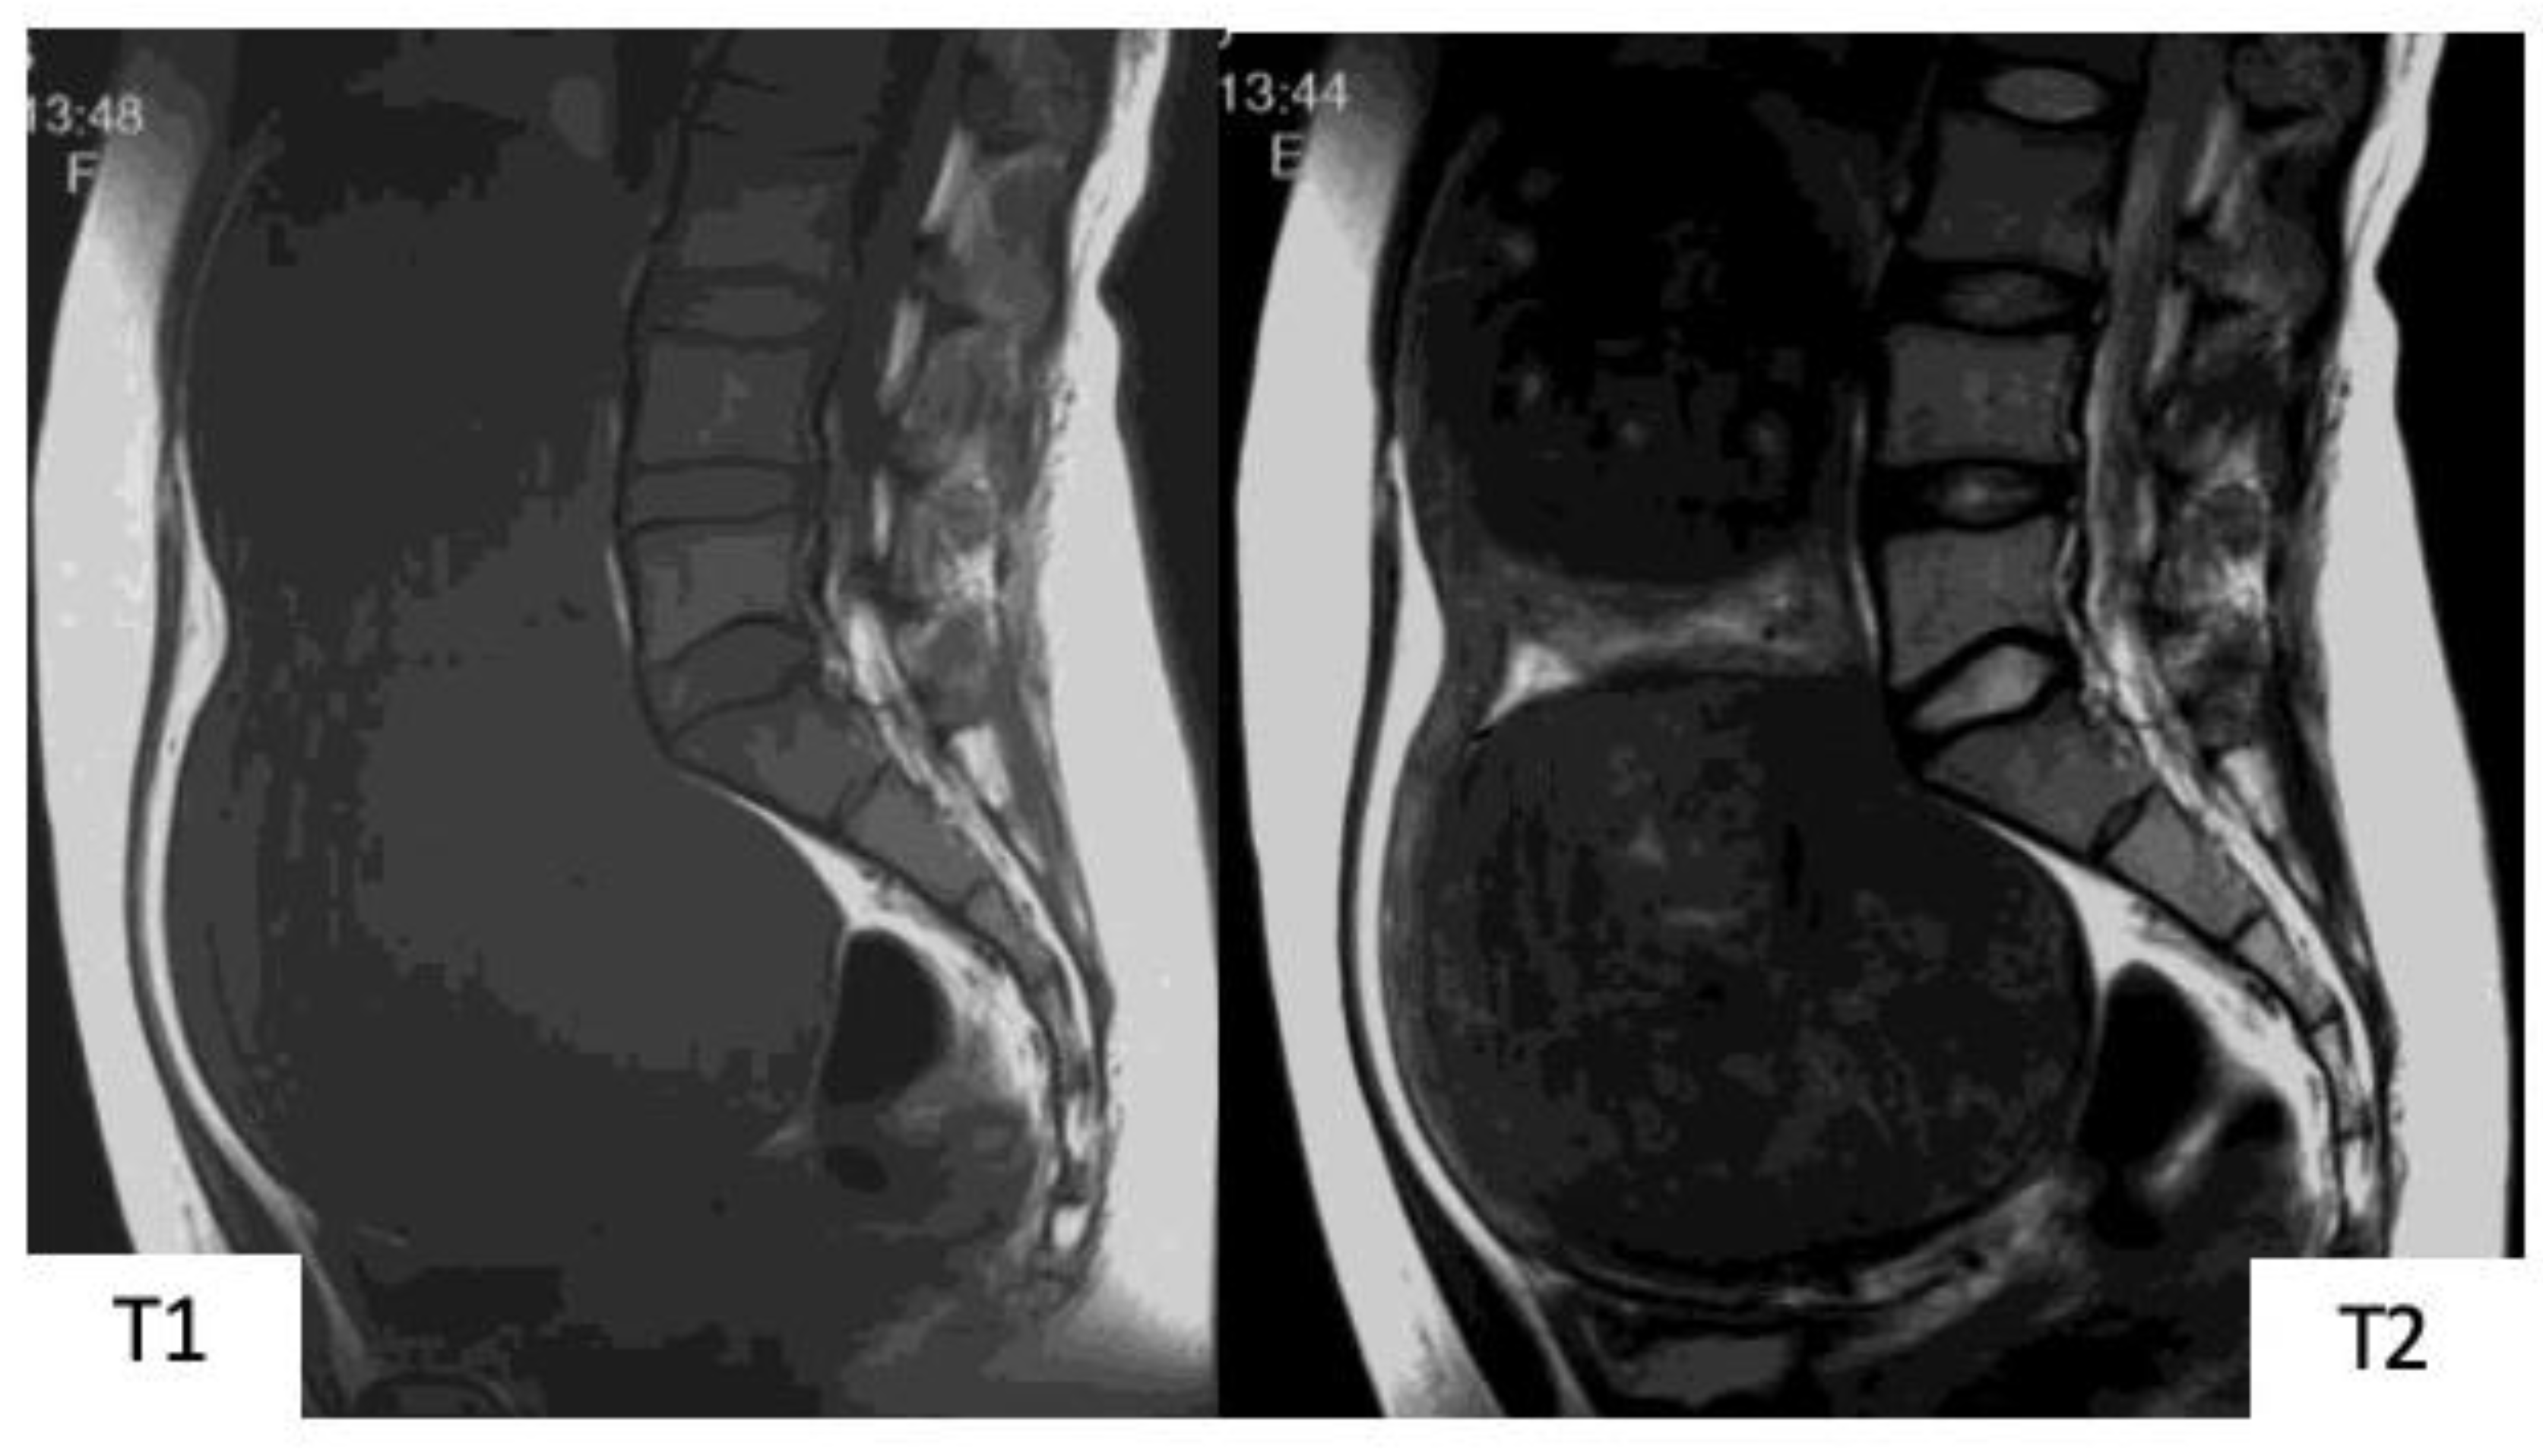

An MRI scan is useful in differentiating between uterine myoma and sarcoma because a typical MR image for myoma exists. That is, uterine myoma shows a clear border, with a mostly spherical shape. In T1WI, there are more equivalent signals or relatively low signals compared to those for normal muscle layer, and in T2WI, mass is depicted in signals that are patently lower than those for normal muscle layer (Figure 1). Confirmation of an MR image enables the diagnosis of myoma. However, when the modification of degeneration is added to a myoma, a completely different image finding is presented than the above-described typical one (Figure 2). Subsequently, the differentiation of such a myoma from uterine sarcoma becomes problematic.

Figure 1.

Typical images of uterine myoma in magnetic resonance images. In T1-weighted images, signals equivalent to or relatively lower than that of the normal myometrium can be observed. In T2-weighted images, signals that are clearly lower than those of the normal myometrium, with resection of almost all spherical masses with clearly defined borders, can be observed.